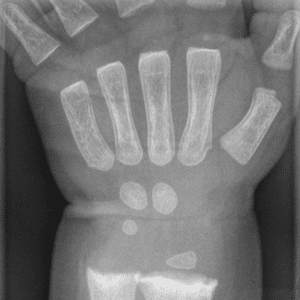

Pediatric Radiographs